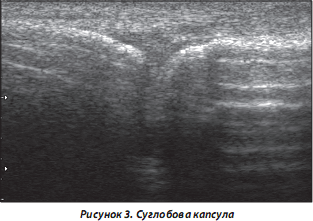

3. Суглобова капсула. У нормі виглядає як контрастна непотовщена гіперехогенна лінія (рис. 3). У більшості випадків при РЗС змінюються УЗ-характеристики (збільшується товщина, з’являються ознаки розволокніння, ча-сткових та суцільних надривів/розривів, витікання синовіальної рідини (СР) (наприклад, при кісті Бейкера).